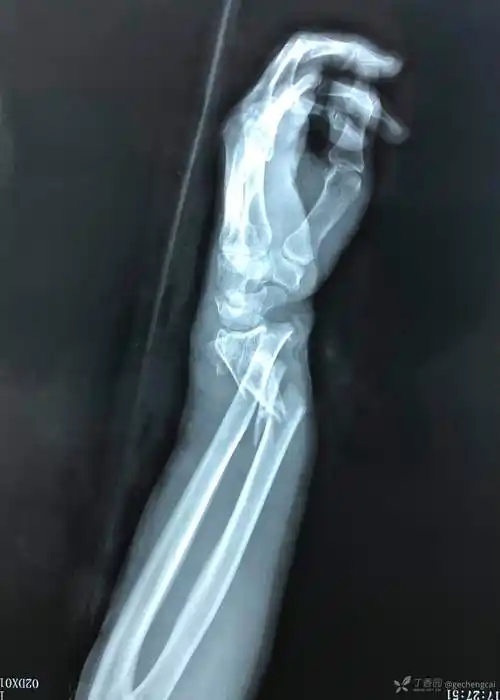

开放性尺桡骨远端粉碎性骨折